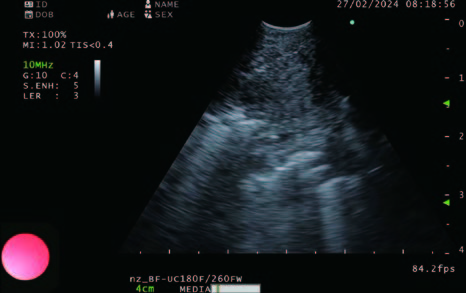

During EBUS-TBNA the position of the needle is clearly visualized and seen as the needle enters the nodes and the subtle artifacts that are related to the stylet moving back and forth can also be observed (Figure 2).

Figure 2